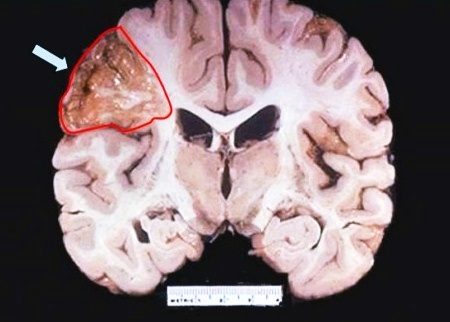

Геморрагический инсульт

Нетравматическое подоболочечное кровоизлияние и субарахноидальное часто относят к одному виду инсульта – геморрагическому. В обоих случаях – это кровоизлияние в мозг. Приступ возникает внезапно, при этом обычные предшествующие симптомы инсульта головного мозга могут отсутствовать. Чаще всего причиной становится гипертоническая болезнь, церебральный атеросклероз или заболевания крови.

В 90% случаев зона кровоизлияния локализуется в области больших полушарий: в передней части. Реже поражается ствол головного мозга или мозжечка – боль возникает в затылочной зоне, задней части шеи. Как правило, происходит разрыв сосуда. Диапедезное нарушение происходит не часто. Возникнуть геморрагический инсульт может даже у ребенка, основной возраст пострадавших – от 35 до 65 лет. К смерти приводит обширное поражение клеток мозга и запоздалое обращение за медпомощью.